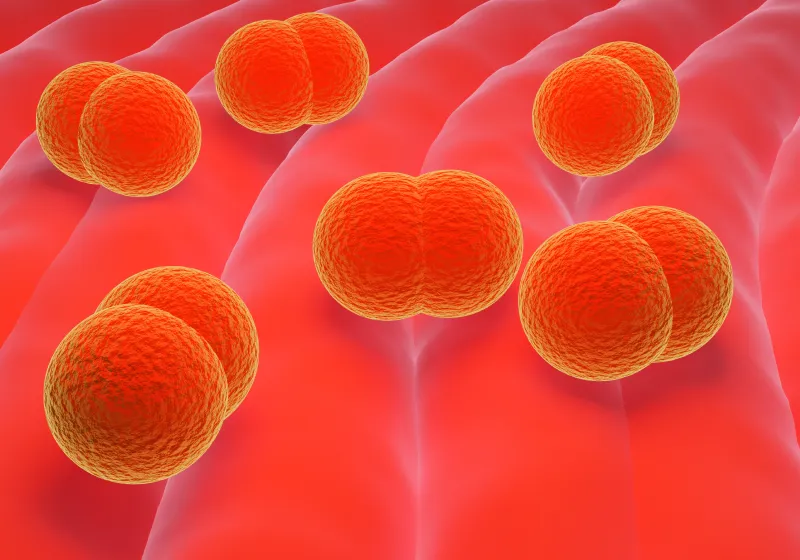

歯周病の発症には、まず「プラーク(歯垢)」と呼ばれる細菌の塊が深く関係しています。

プラークは食べかすの汚れではなく、わずか1mgの中に約10億個もの細菌が存在するといわれる“生きた細菌の集合体”です。これらの細菌が出す毒素が歯ぐきや骨に炎症を引き起こし、歯を支える土台を少しずつ壊していきます。

プラークを放置すると、唾液中のカルシウムやリン酸と結びついて「歯石」へと変化します。

歯石は非常に硬く、歯の表面がザラザラしているため、新たなプラークが付きやすい状態をつくり出します。

さらに、歯石は歯ブラシでは除去できず、歯科医院で専用の器具を使ったスケーリング(歯石除去)が必要になります。

こうしてプラークと歯石が歯と歯ぐきの境目に蓄積すると、細菌が酸素の少ない環境(歯周ポケット)で繁殖し、炎症を悪化させていきます。初期には「歯ぐきからの出血」程度の軽い症状でも、放置すると膿が出たり、歯がぐらついたりと進行し、やがて重度歯周病へと移行してしまうのです。